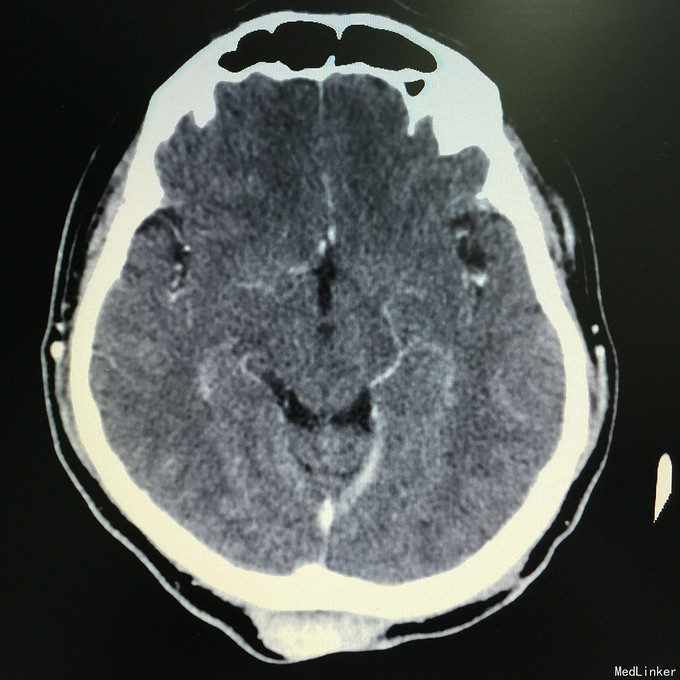

查体:头枕部可见单个肿物,半圆形,约鸡蛋大小,质地中等,边界清,无糜烂、渗出、压痛。头枕部可见单个半环状手术疤痕,长约15cm,无糜烂、渗出、脓性分泌物,无恶臭。余查体无特殊。 辅助检查:抽血检查未见明显异常。头颅CT增强示:“低度恶性纤维黏液样肉瘤”切除术后,枕部皮下软组织影,结合病史,考虑肿瘤复发,建议MR检查。彩超:双侧颈部见多个小淋巴结,双侧腋窝未见明显异常肿大淋巴结。双侧腹股沟见多个小淋巴结。